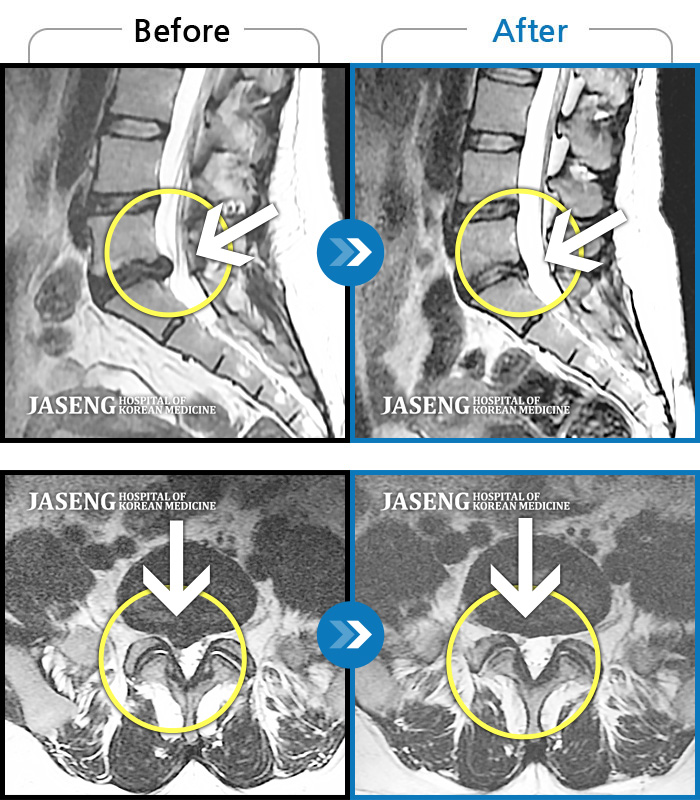

MRI 치료사례

허리 통증과 오른쪽 다리 당김